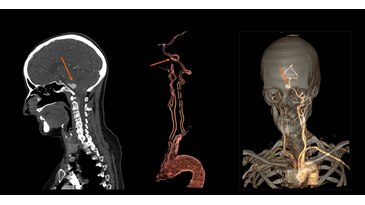

Carotids, assessment of aneurism at 1.8 mSv1

Circle of Willis